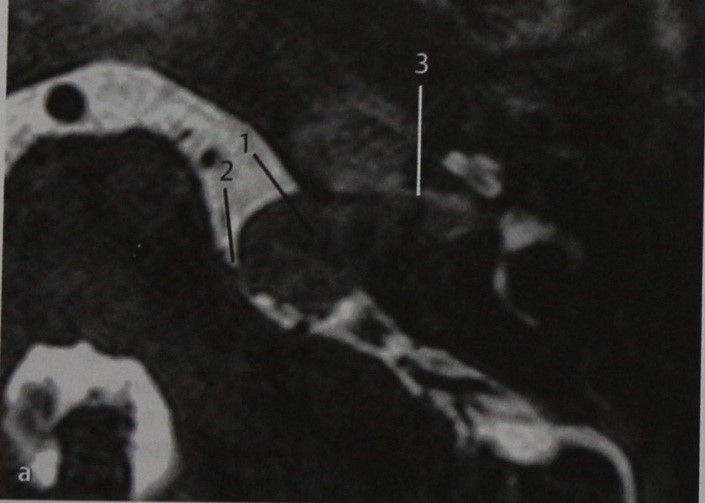

Пациент с медленно прогрессирующей односторонней нейросенсорной тугоухостью.

МРТ: Т2-взвешенное изображение в горизонтальной проекции. Опухоль имеет средние размеры (1), расположена в области мостомозжечкового угла и отчасти во внутреннем слуховом проходе и касается ствола мозга (2). Хотя нет четких признаков, указывающих на то, что латеральная часть внутреннего слухового прохода, т.е. его дно, заполнена жидкостью, какое-то количество ее все же имеется (З), сама опухоль не выходит за пределы медиальной части внутреннего слухового прохода.